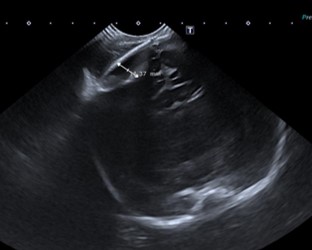

Primera gestación de una madre sana de 36 años. A las 39 semanas de gestación nace mediante parto eutócico con vacuum, tras presentación cefálica, por bradicardia fetal mantenida. Requiere reanimación inicial con IPPV nasal. Prueba de Apgar 3/6/9; pHau: 6.58. Peso de nacimiento: 3195g (p50), longitud: 50cm (p50) y perímetro cefálico: 34cm (p25-p50). USc cerebral a las 12h de vida (Figura 1 A).

Nuestra paciente presenta un hematoma epidural (HE), hallado de manera casual en la ultrasonografía cerebral (USc) realizada en el contexto de una paciente con encefalopatía hipóxico–isquémica moderada.

Mediante USc, justo debajo del cefalohematoma parietal derecho, se apreció el HE de 11 mm de diámetro (Figura 1A).  La colección de sangre se sitúa entre la duramadre y el calvario.

Figura 1 A. USc. Corte coronal.